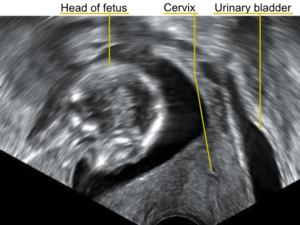

| A transvaginal ultrasonography showing a retroverted uterus during pregnancy. The cervix lies posteriorly to the urinary bladder, and the uterus normally extends superiorly from it, but the direction of the body of the fetus reveals that the uterus extends backwards. | |